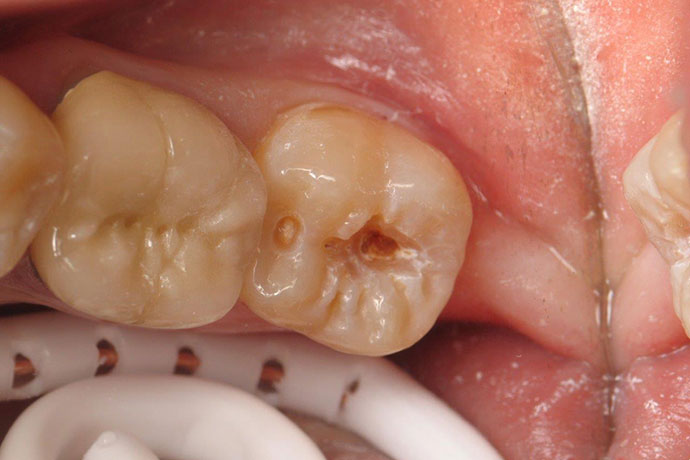

Crowns

Before